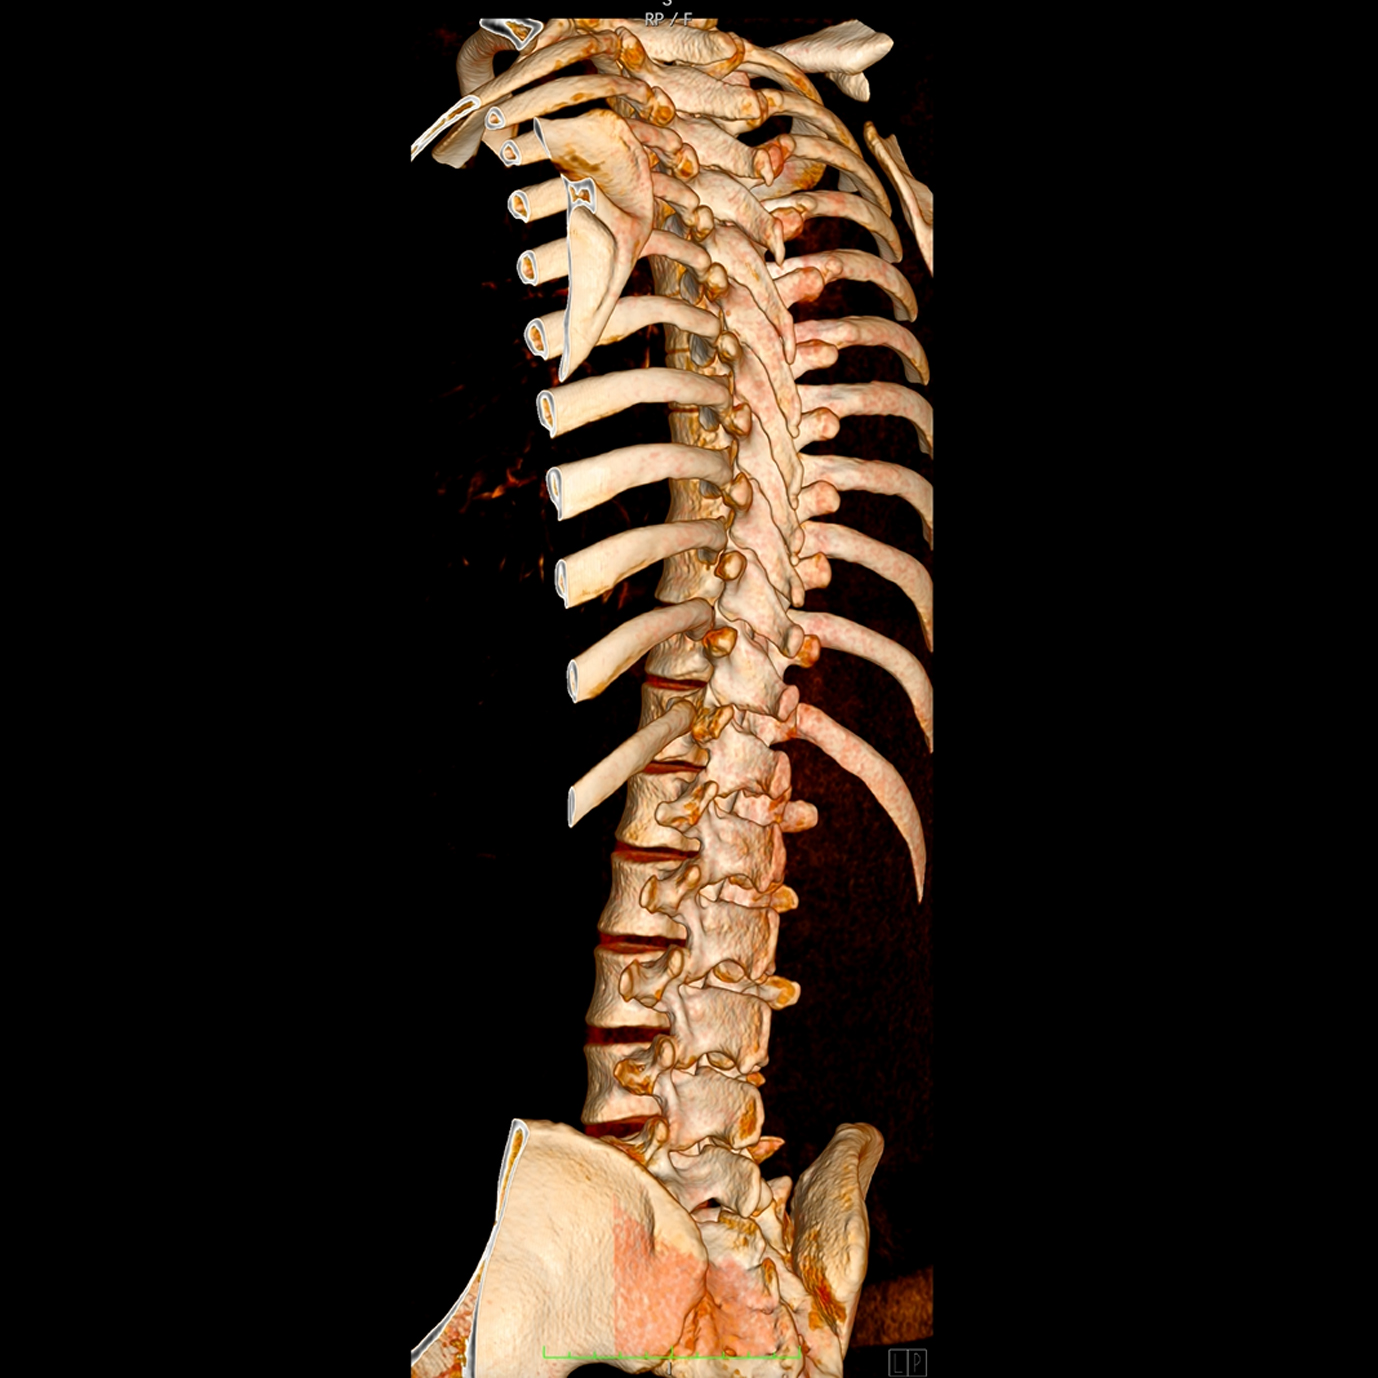

Ejemplos de estudios realizados en nuestra clínica.

con precisión avanzada para un diagnóstico confiable